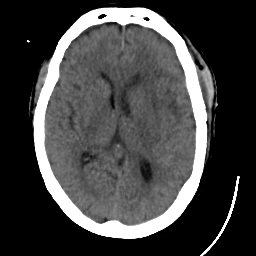

Meningioma: Roentgen-ray CT #1 -- Slice #11

[Home][Help][Clinical] Slice 11